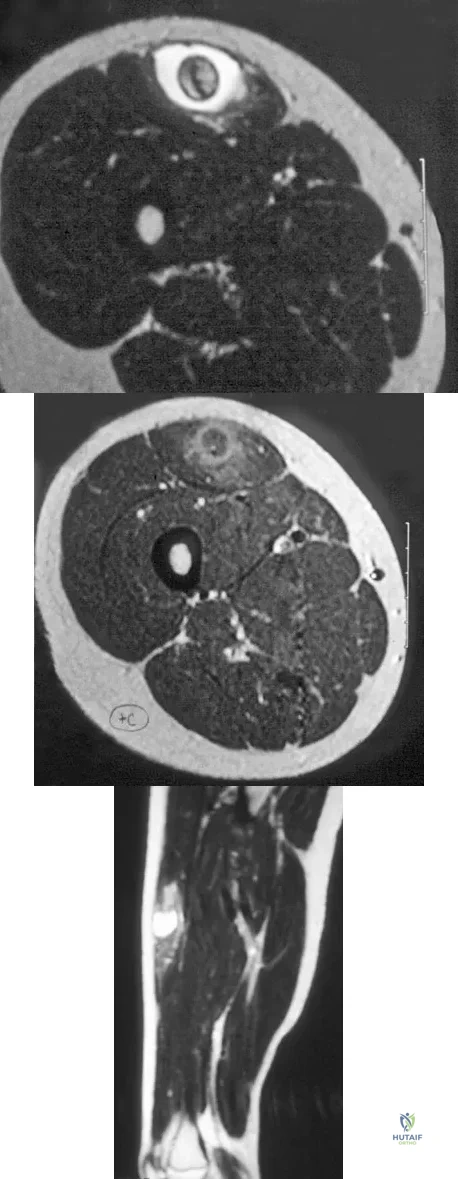

A 14-year-old girl reports a 3-week history of anterior thigh pain and a palpable mass after sustaining a soccer-related injury. Examination reveals a tender, firm mass in the midportion of the rectus femoris. MRI scans are shown in Figures 39a through 39c. What is the most appropriate management?

Explanation